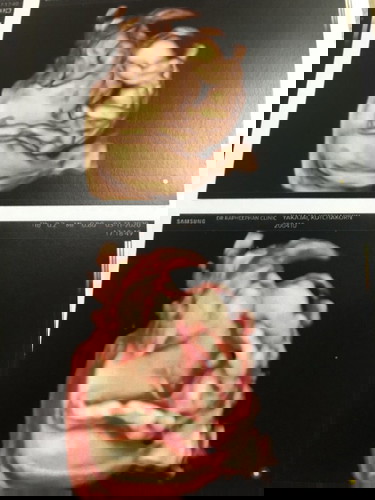

อายุครรภ์15สัปดาห์3วัน เจอภาวะรกเกาะต่ำ

เมื่อวันก่อนมีอาการปวดท้องเหมือนมีประจำเดือนค่ะ สักพักมีเลือดออกเลยไปพบหมอ หมอบอกมีภาวะรกเกาะต่ำ เด็กหัวใจปกติดี แต่หมอไม่ได้ฉีดยารึให้ยาอะไรมา แต่ติดตามอาการอีก2อาทิตย์ แต่พอกลับบ้านมาก็มีเลือดออกเยอะกว่ารอบแรกค่ะแล้วหยุด แล้วก็มาแบบกะปริบกะปรอย อยากทราบว่าอันตรายมั่ยค่ะ บ้านไหนเคยมีประสบการณ์รกเกาะต่ำบ้างแนะนำหน่อยค่ะ